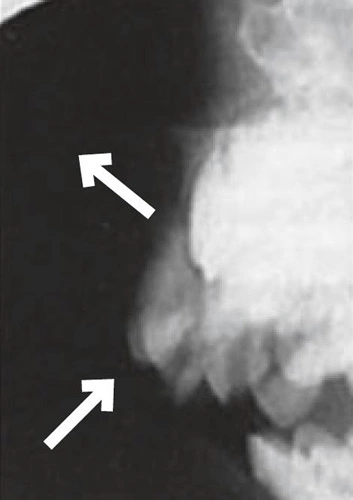

Wie bei der bleibenden Dentition stellen die Intrusionen ein besonderes Problem dar: Bei 4 bis 22% der Traumata im Milchgebiss bei sehr kleinen Kindern im Alter von 1 bis 3 Jahren [15] resultiert eine relevante Schädigung des Zahnkeimes und damit nachfolgenden Zahnes [16] wie Schmelzhypoplasien, Kronenverlagerungen, odontomähnliche Verformungen, Kronen-/Wurzelabknickung, Einstellung der Wurzelbildung, Infektion des Zahnkeimes und Schmelzschädigung sowie Durchbruchsstörungen beim bleibenden Zahn (Abb. 6a u. b).

Prinzipiell steht bei der Intrusion die abwartende Therapie mit der Möglichkeit einer spontanen Reeruption innerhalb weniger Wochen der zügigen Entfernung gegenüber, die den Druck auf den bleibenden Zahn sofort mindert, aber oft nicht ohne Narkose erfolgen kann. Randomisierte und damit hochwertige Vergleichsstudien existieren nicht und somit kann nur anhand von biologischer Plausibilität geraten werden, bei unkomplizierten Fällen primär der Reeruption eine Chance zu geben. Die Empfehlung, intrudierte Milchzähne reeruptieren zu lassen, basiert auf der bukkalen Position der Intrusion zum Zahnkeim (siehe Abb. 5).